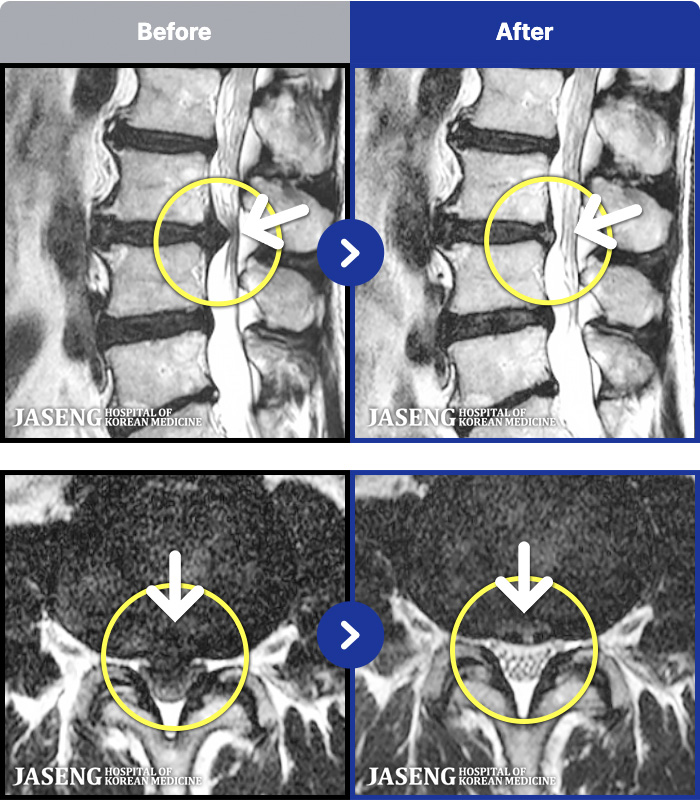

1,286 MRI ũ ʸ Ȯϼ.

ȯںп Ǹ ǿ ԿǾ, ο ġ ۿ Ƿ ġḦ Ͻñ ٶϴ.